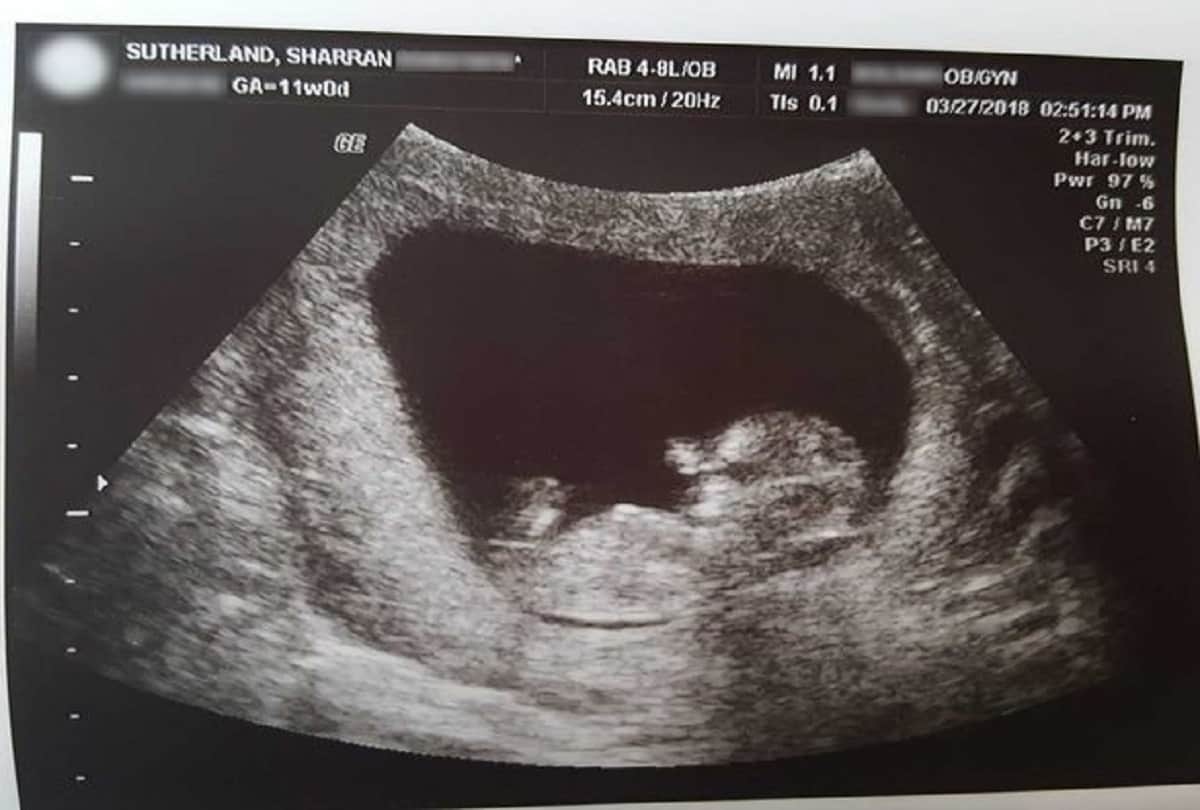

टूटे हुए दिल के साथ एक माता-पिता ने गर्भपात हुए बच्चे की तस्वीरें सोशल मीडिया पर साझा की हैं। जिसे उन्होंने 14 सप्ताह की गर्भावस्था के बाद खो दिया था। एक बहादुर मां ने अपने मृत बेटे की तस्वीरों को यह साबित करने के लिए साझा किया है कि डॉक्टरों के 'मेडिकल कचरा' कह दिए जाने के बाद उन्होंने अपने बच्चे की सही तस्वीरें साझा की है।

40 वर्षीय शरण सुथरलैंड आश्चर्यचकित था कि कैसे 'परिपूर्ण' बेटा मिरान उसके गर्भावस्था में 14 सप्ताह तक मरने के बावजूद था। उसने उसे हाइड्रेंजिया झाड़ी के नीचे एक फूल के गमले में दफनाने से पहले एक सप्ताह के लिए उसे फ्रिज में रखा था।